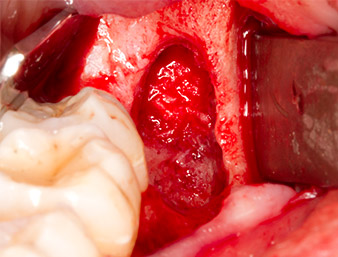

root remnant 38

Fig. 7: The root remnant 38 (LL8) is well exposed in its alveole for subsequent removal.

Using an instrument for periodontal debridement (Piezomed P1), the periodontal ligament space of the radix relicta was then widened minimally (Fig. 8).

The same activated instrument was inserted into the root canal and loosened the fragment as a result of its micro-oscillating vibrations (Fig. 9, 10).